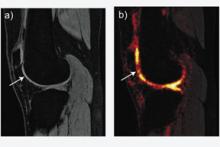

New and improved techniques in magnetic resonance imaging (MRI) are popping up every day, stemming from innovations developed by physicians and manufacturers alike. Many of these new techniques are especially conducive to high-field systems — 3.0 Tesla (3T) systems and higher.

3T Advances